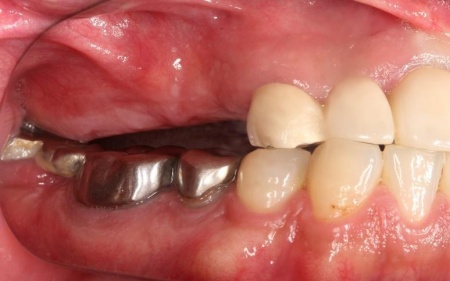

また、右上前歯も1本欠損しており、両隣の歯を土台として橋を渡すように連結した被せ物「ブリッジ」が装着されていましたが、土台となっている右上前歯2本(中切歯、犬歯)が割れており、温存が難しい状態です。

まず、右上前歯2本を抜きます。

次に、右上奥歯と前歯にインプラント治療を行いました。

右上奥歯は、歯周病でインプラントを埋入するために必要な骨が不足していたため、上顎の奥にある上顎洞の底を押し上げて人工の骨を補う「サイナスリフト」という骨造成を併用しています。

右上前歯も同様に骨が少なかったため、こちらは骨の移植を行って骨量を確保したのち、インプラントを埋入しました。

インプラントが骨にしっかりとなじんだことを確認したら、白くて強度の高い人工歯「ジルコニアクラウン」を装着しました。